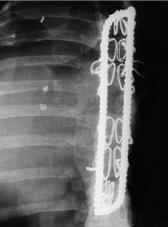

Rectángulo modelado con dispositivo de cierre “Codo de Dufoo”

Una vez que iniciamos el uso de la técnica del Dr. Eduardo Luque R. para la estabilización vertebral, encontramos que la técnica presentaba un problema. Al ajustar los alambres sublaminares a las barras laterales, se desplazaban hacia la línea media, perdiendo estabilidad y facilitando la rotación. Además, las barras rectas forzaban las curvaturas vertebrales naturales, originando “espaldas planas”. Esto se solucionó al diseñar una barra en forma de rectángulo, cerrando los extremos firmemente con un codo, lo que nos permitía modelarla sobre las curvaturas de la región vertebral, mejorando la estabilidad sin deformar el perfil del raquis. Esta técnica sigue siendo utilizada en la actualidad, para algunos pacientes. Resultados publicados.

Sistema “SD” de instrumentación vertebral

Durante el periodo de estabilización vertebral con el uso de tornillos transpediculares, se presentaron dificultades con los tornillos de base fija, lo que obligaba a la recolocación frecuente del tornillo por no estar alineado con la barra. Con la aparición de los tornillos con base móvil, este problema se volvió menos frecuente. Sin embargo, consideramos que “el raquis del paciente debe ajustarse al perfil del implante”. Este criterio fue discutido con diferentes asesores de los centros de investigación mencionados previamente.

Por ello, diseñamos un sistema de barras sujetas con tornillos transpediculares, permitiendo que el ensamble sea ajustable al ángulo de colocación del tornillo transpedicular, a la curvatura vertebral, a la distancia interpedicular y a la distancia entre segmentos vertebrales. Con esta flexibilidad de orientación en los ensambles, logramos que el sistema de estabilización “SD” se adapte a la anatomía vertebral del paciente sin modificar la resistencia de la instrumentación ni forzar los ensambles. Resultados publicados.